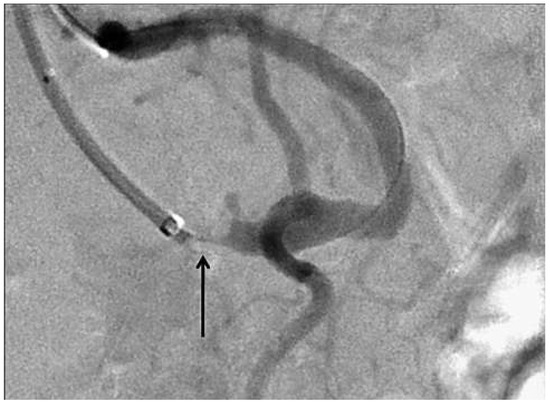

The diagnostic workup icluded gastroscopy and colonoscopy, demonstrating lesions compatible with chronic non-transmural gastric and intestinal ischaemia which were confirmed at biopsy. Computed tomographic angiography (Figure 1) showed estimated 75– 90% stenosis at the origin of the coeliac trunk and estimated 75% stenosis at the origin of the superior mesenteric artery, while the inferior mesenteric artery appeared to be free of significant stenosis. Surgical consultants deemed the patient not a candidate for surgery.

Figure 1.

Computed tomography angiography reconstructions showing severe calcified stenosis at the origin of the coeliac trunk (single arrow) and massive calcifications at the origin of the superior mesenteric artery (double arrow).